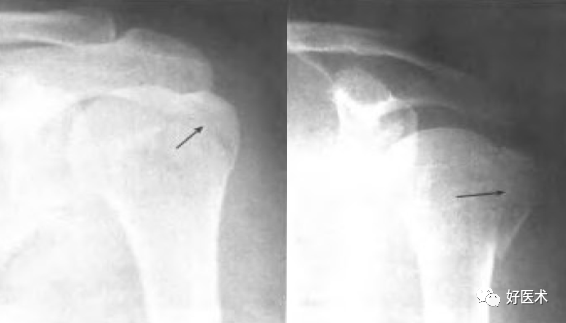

附:大结节撕脱骨折内固定

适用经手法复位失败,骨折移位超过1cm者;骨折块拉至肩峰下。

麻醉:颈丛麻醉 。

体位:仰卧位,患肩垫高与手术台成30°角。

操作方法:

切口:自肩峰外侧缘,约5cm,平行于三角纤维方向。

劈开三角肌纤维,切开三角肌肩峰和锁骨外侧端的附着点,显露结节部

在结节上用3.0钻头朝肱骨头方向钻孔,深约12-20mm

用钛丝穿过肩袖

将钛丝缠绕螺钉钉帽一圈

选择合适长度螺钉

拧入干预螺钉至钉帽外露3mm深度

用钢丝钳把钛丝缠绕拧紧,检查骨折复位情况

冲洗伤口,逐层缝合肌肉,皮肤切口

曲肘90°位三角巾悬吊制动,2周后开始被动活动